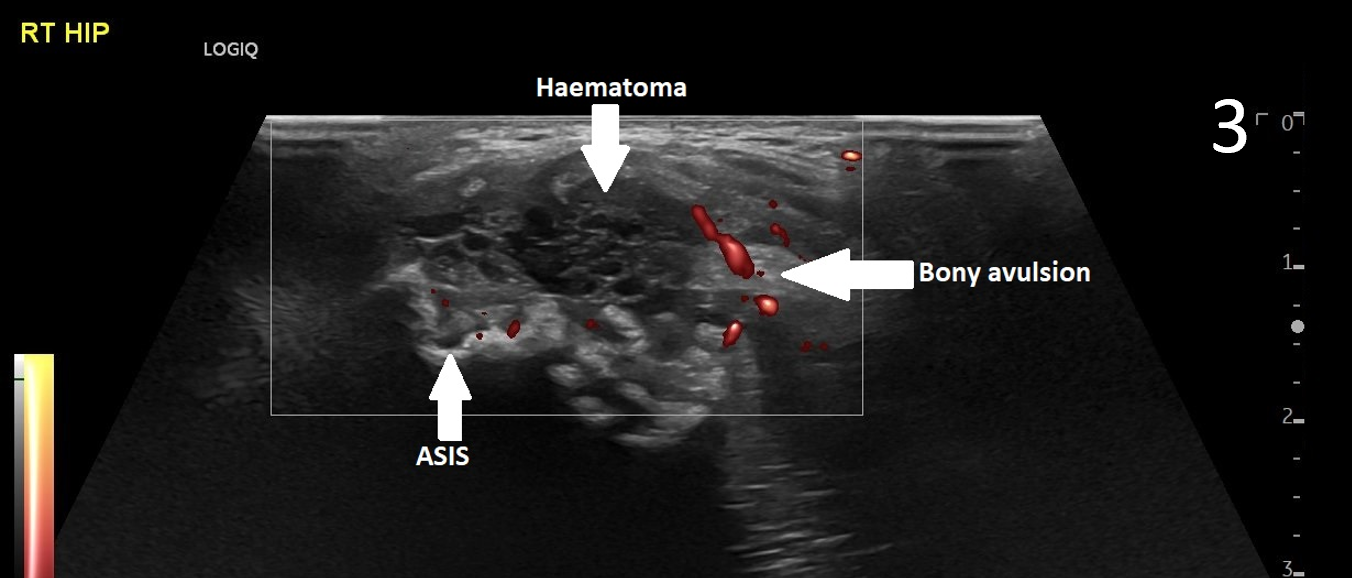

The patient was focally tender in the right iliac fossa at the level of the anterior superior iliac spine (ASIS). At this site, there was muscle fibre disruption and a haematoma at the insertion of the sartorius tendon with minimal retraction (Figure 2). There was cortical irregularity at the ASIS and a bony fragment within the retracted tendon and also neovascularisation here on power Doppler (Figure 3). On comparison to the contralateral side, there was altered architecture of the sartorius muscle with a clear defect while the left side looked normal (Image 4). Ultrasound appearances in keeping with a sartorius tendon avulsion. This was treated conservatively with rest, analgesia and a return to normal activities after two months. Surgical interventions are uncommon and are reserved for when the fracture fragment has migrated more than 3cm.